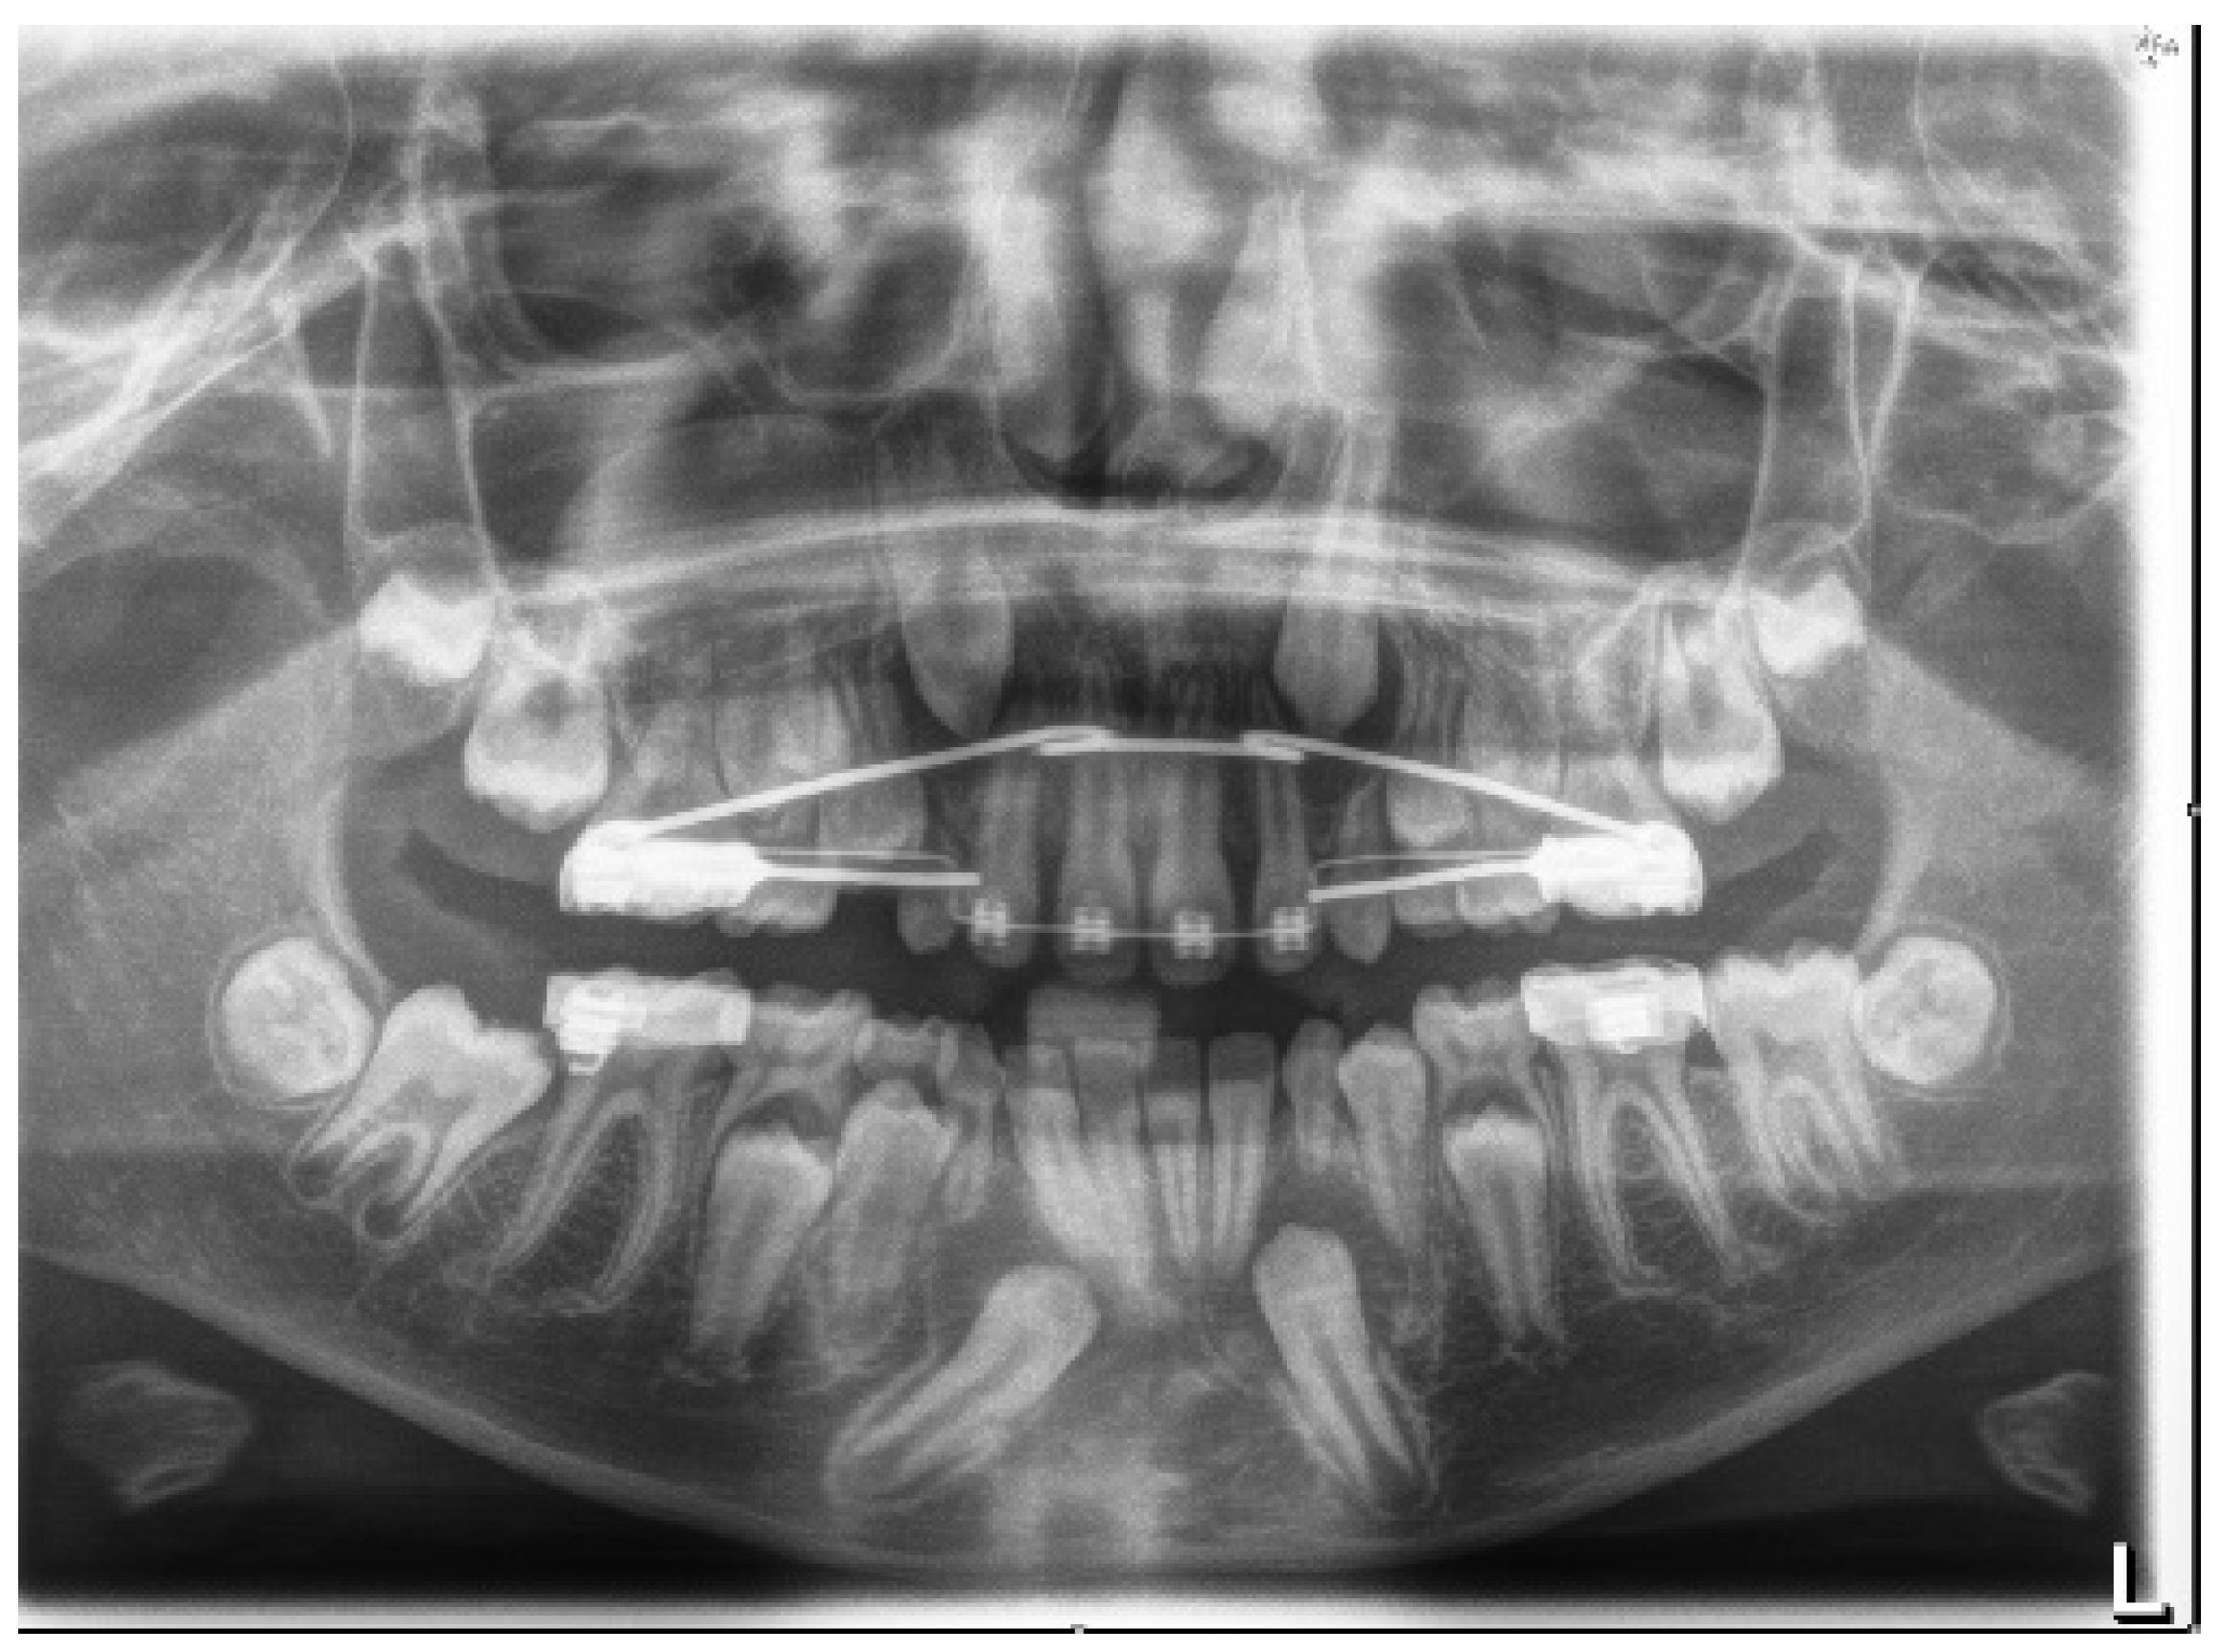

4.1. Phase 1: Initial Orthodontic Treatment

4.2. Phase 2: Surgical Technique

4.3. Orthodontic Traction

4.4. Phase 3: Final Orthodontic Treatment